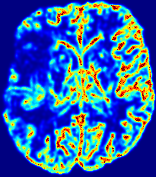

LesionRefer to captionRefer to captionRefer to captionRefer to captionRefer to captionRefer to caption𝐕rgbsubscript𝐕𝑟𝑔𝑏{\bf{V}}_{rgb}Refer to captionRefer to captionRefer to captionRefer to captionRefer to captionRefer to caption𝐕2subscriptnorm𝐕2{\|\bf{V}}\|_{2}Refer to captionRefer to captionRefer to captionRefer to captionRefer to captionRefer to captionRefer to caption3.53.53.52.82.82.82.12.12.11.41.41.40.70.70.70.00.00.0(mm/s)𝑚𝑚𝑠(mm/s)D𝐷DRefer to captionRefer to captionRefer to captionRefer to captionRefer to captionRefer to captionRefer to caption0.0200.0200.0200.0160.0160.0160.0120.0120.0120.0080.0080.0080.0040.0040.0040.0000.0000.000(mm2/s)𝑚superscript𝑚2𝑠(mm^{2}/s)Slice #1Slice #2Slice #3Slice #4Slice #5Slice #6

Figure 4: PIANO feature maps for another patient in the ISLES 2017 training set, where the lesion is located in the right hemisphere. Top row: segmented stroke lesion region (white) on different slices. The corresponding slices for the PIANO feature maps are shown in the following rows.

For a better insight into an estimated velocity field 𝐕𝐕{\bf{V}} and diffusion field 𝐃𝐃{\bf{D}}, we compute the following maps: (1) 𝐕rgbsubscript𝐕𝑟𝑔𝑏{\bf{V}}_{rgb}: Color-coded orientation map of 𝐕=(Vx,Vy,Vz)T𝐕superscriptsuperscript𝑉𝑥superscript𝑉𝑦superscript𝑉𝑧𝑇{\bf{V}}=(V^{x},V^{y},V^{z})^{T}, obtained by normalizing 𝐕𝐕{\bf{V}} to unit length and mapping its 3 components to red, green, blue respectively; (2) 𝐕2subscriptnorm𝐕2\|{\bf{V}}\|_{2}: 222 norm of 𝐕𝐕{\bf{V}}; (3) D𝐷D: scalar field in Eq. 5.

Fig. 3 and Fig. 4 show the PIANO feature maps estimated from two ISLES 2017 patients: all are highly consistent with the lesion in both cases. Details of the blood flow trajectories are revealed in 𝐕rgbsubscript𝐕𝑟𝑔𝑏{\bf{V}}_{rgb} by the ridged patterns and the sharp changes of colors in the unaffected (right) hemisphere, while the flat patterns appearing within the lesion provide little directional information about the velocity and indicate low velocity magnitudes. Velocity magnitudes are more directly visualized via 𝐕2subscriptnorm𝐕2\|{\bf{V}}\|_{2}, from which one can easily locate the lesion where 𝐕2subscriptnorm𝐕2\|{\bf{V}}\|_{2} is low. D𝐷D also indicates lower diffusion values in the lesion, though with less contrast potentially due to the fact that it captures the accumulated effect of CA diffusion at the voxel-level.